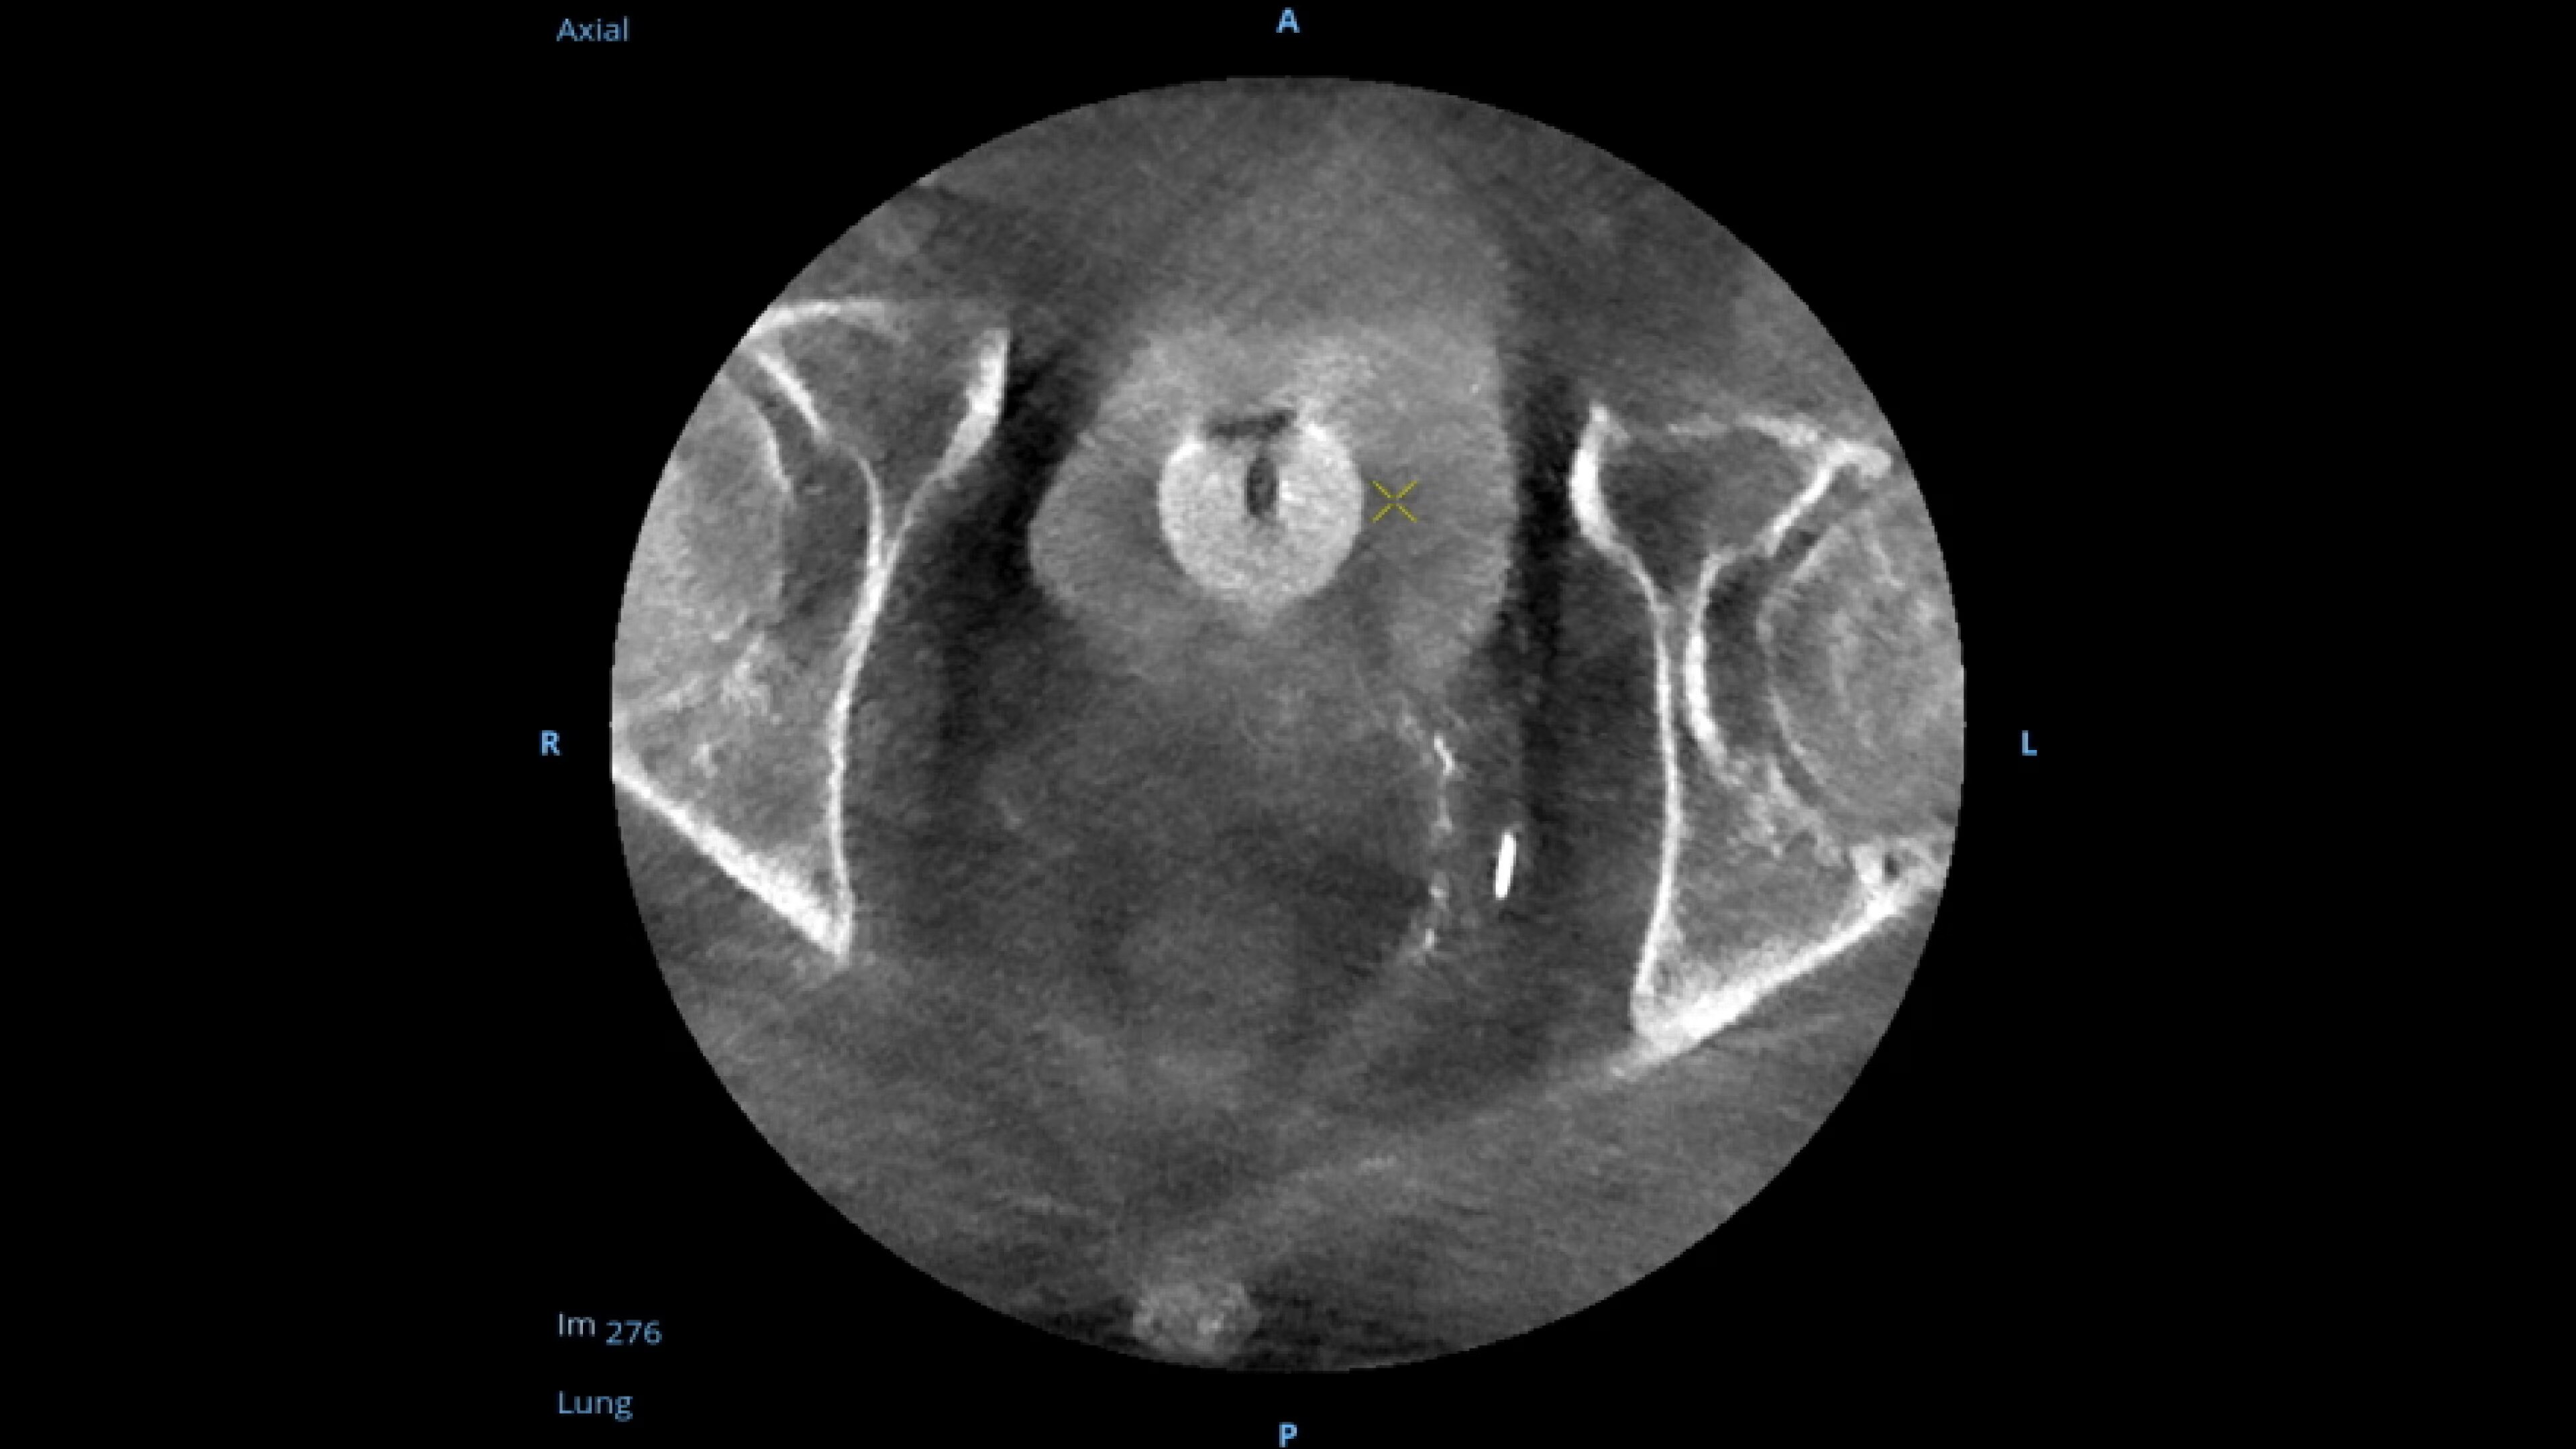

When visual confirmation during a procedure is desired, the

OEC 3D can provide 3D volumes with five perspectives.

Analyze CT-like images with the OEC 3D Volume Viewer which includes Multi-Oblique, Area Measure, Window Level/Window Width, rotate, zoom, and more for quick and comprehensive visualization.